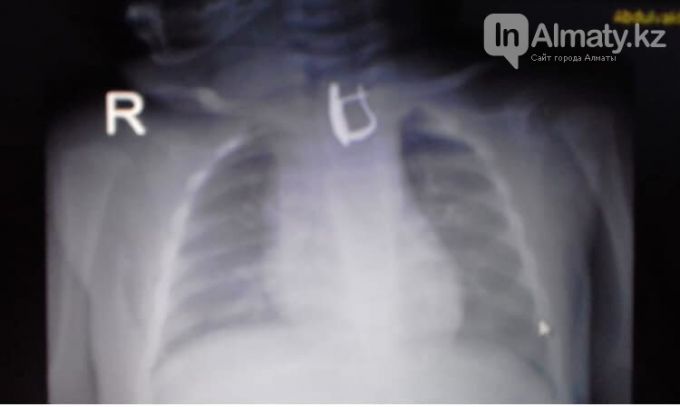

«Дәрігерлердің қарауынан соң рентген оның өңешінде бөгде зат тұрып қалғанын көрсетті. Нәресте «Балалар шұғыл медициналық жәрдем орталығы» ауруханасына жіберілді. Түскі 14:00 шамасында баланың өңешінен эндоскопиялық жолмен сырға алынып тасталды. Қазір жағдайы жақсы, бірқалыпты. Уақытында көрсетілген көмектің арқасында баланың өңешінде жара пайда болған жоқ. Қан аққан жоқ», - делінген хабарламада.